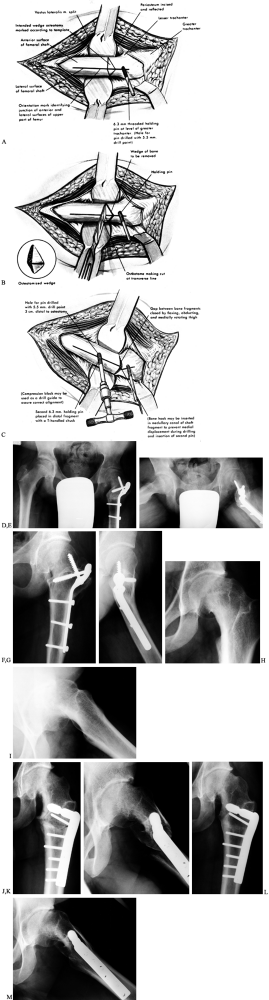

Figure 172.1. Two common methods of magnitude measurement for slipped capital femoral epiphysis (SCFE). A:

Measurement of the amount of displacement of the epiphysis relative to the metaphyseal width. The SCFE is considered mild if the measured tip is less than 33%, moderate if it is 33% to 50%, and severe if it is more than 50%. B: The head–shaft angle is measured on the frog-lateral pelvis radiograph of the pelvis to determine the degree of the slip, which is calculated by subtraction of the angle on the normal side from the angle of the affected hip: 49° – 12° = 37°. (From Aronson DD, Carlson WE. Slipped Capital Femoral Epiphysis: A Prospective Study of Fixation with a Single Screw. J Bone Joint Surg Am 1992;74:810, with permission.) |

the epiphyseal–shaft angle, which more accurately reflects the true

slip magnitude, is used (78) (Fig. 172.1B). This angle is measured on the frog-lateral pelvis radiograph by the following method.

The first involves the amount of epiphyseal displacement relative to

the metaphysis (16) (Fig. 172.1A).

A mild SCFE is one with less than 33% displacement; moderate, 33% to

50%; and severe, greater than 50%. This can be measured on both the AP

and the lateral radiographs. In the case of a stable SCFE of many

months’ duration, remodeling of the femoral neck makes this measurement

less reliable, underestimating the true magnitude of slip.